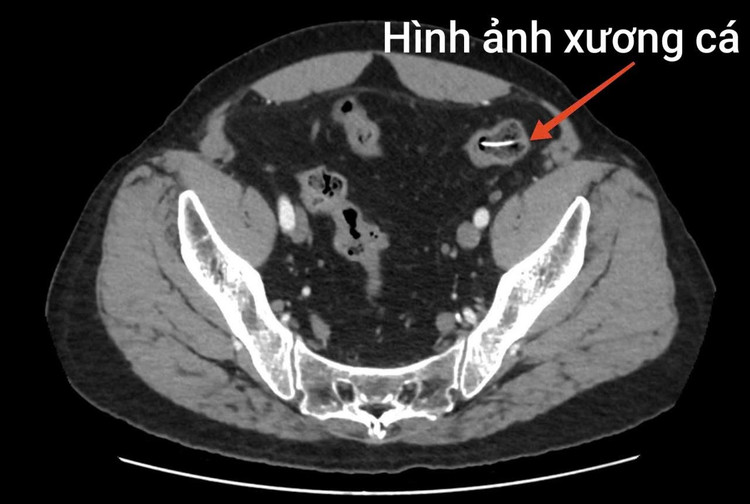

Kết quả xét nghiệm và chẩn đoán hình ảnh cho thấy tình trạng nguy hiểm của bệnh nhân: Chỉ số bạch cầu tăng cao (14.6 10^9/L), hình ảnh nhiều dị vật hình xương cá nằm ngang đoạn ruột non. Kèm theo vị trí đại tràng xuống vùng hố chậu phải trong lòng có một dải tăng tỷ trọng (kích thước 24 x 6mm). Bệnh nhân được chẩn đoán thủng ruột non do dị vật, với bệnh nền bệnh phổi tắc nghẽn mạn tính và được chỉ định phẫu thuật cấp cứu.

Hình ảnh xương cá đâm thủng ruột bệnh nhân/Ảnh BV Bệnh Nhiệt đới Trung ương

Trong quá trình mổ, ê-kíp phẫu thuật phát hiện ổ bụng bẩn nặng, nhiều giả mạc, dịch ổ bụng đục, tập trung ở hạ vị – hố chậu phải. Tại vị trí ruột non cách góc hồi manh tràng khoảng 1 mét, có dị vật hình xương cá dài khoảng 4cm chọc thủng ruột non tạo thành 01 lỗ thủng đường kính khoảng 0,5cm.